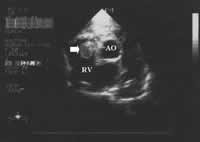

图3 UCG示右室内肿块(↑)。RV=右室,AO=主动脉

实验室检查 血常规 白细胞11.4×109/L,中性粒细胞89.3%,血红蛋白131 g/L,血小板314×109/L;尿常规、便常规+潜血正常。丙氨酸转氨酶(ALT)497 U/L,天冬氨酸转氨酶(AST)532 U/L,碱性磷酸酶(ALP)186 U/L,谷氨酰转肽酶(GGT)136 U/L,总胆红素(TBik)1.63 mg/dk(正常值1.3 mg/dk),直接胆红素(DBik)0.80 mg/dk,白蛋白(ALB)33 g/L,白蛋白/球蛋白(A/G)1.0,乳酸脱氢酶(LDH)866 U/L,血清肌酐、尿素氮正常;凝血酶原时间18.1 s,激活的部分凝血活酶时间27.2 s;乙肝表面抗原(HBsAg)、抗HIV抗体(-)。B超:胰腺体部5.7 cm×4.3 cm低回声占位,回声欠均匀;肝脏回声均匀,胆管无扩张;腹水。CT(图1):双侧胸腔积液,下肺实变;胰体部软组织肿块,胰腺癌可能大,腹水,无腹膜后淋巴结肿大。心电图(ECG):房室交界性心律,短阵房性心动过速,伴室性期前收缩,呈二联律。超声心动图(UCG):下腔静脉(IVC)明显增宽(内径29 mm),其内可见实质占位回声,右房(RA)、右室(RV)及RV流出道内分别见61 mm×22 mm、32 mm×21 mm、30 mm×23 mm不均质的实质肿块(其中RA内充满占位),考虑肿瘤回声;左室收缩功能(射血分数54%)及室壁运动未见异常,左房轻度增大(内径41 mm),轻度肺动脉高压(收缩压46 mmHg),少量心包积液(图2、3)。考虑胰腺肿瘤(胰腺癌可能性大)心脏转移诊断基本成立。本应进一步查CA199以支持胰腺癌诊断,行胸腹部增强CT、头颅CT、核素骨扫描除外其他部位转移的可能,为手术做准备。但因患者病情危重(随时有RV流出道梗阻加重、猝死可能),手术风险极大,且家庭经济困难,家属表示放弃进一步治疗离院。